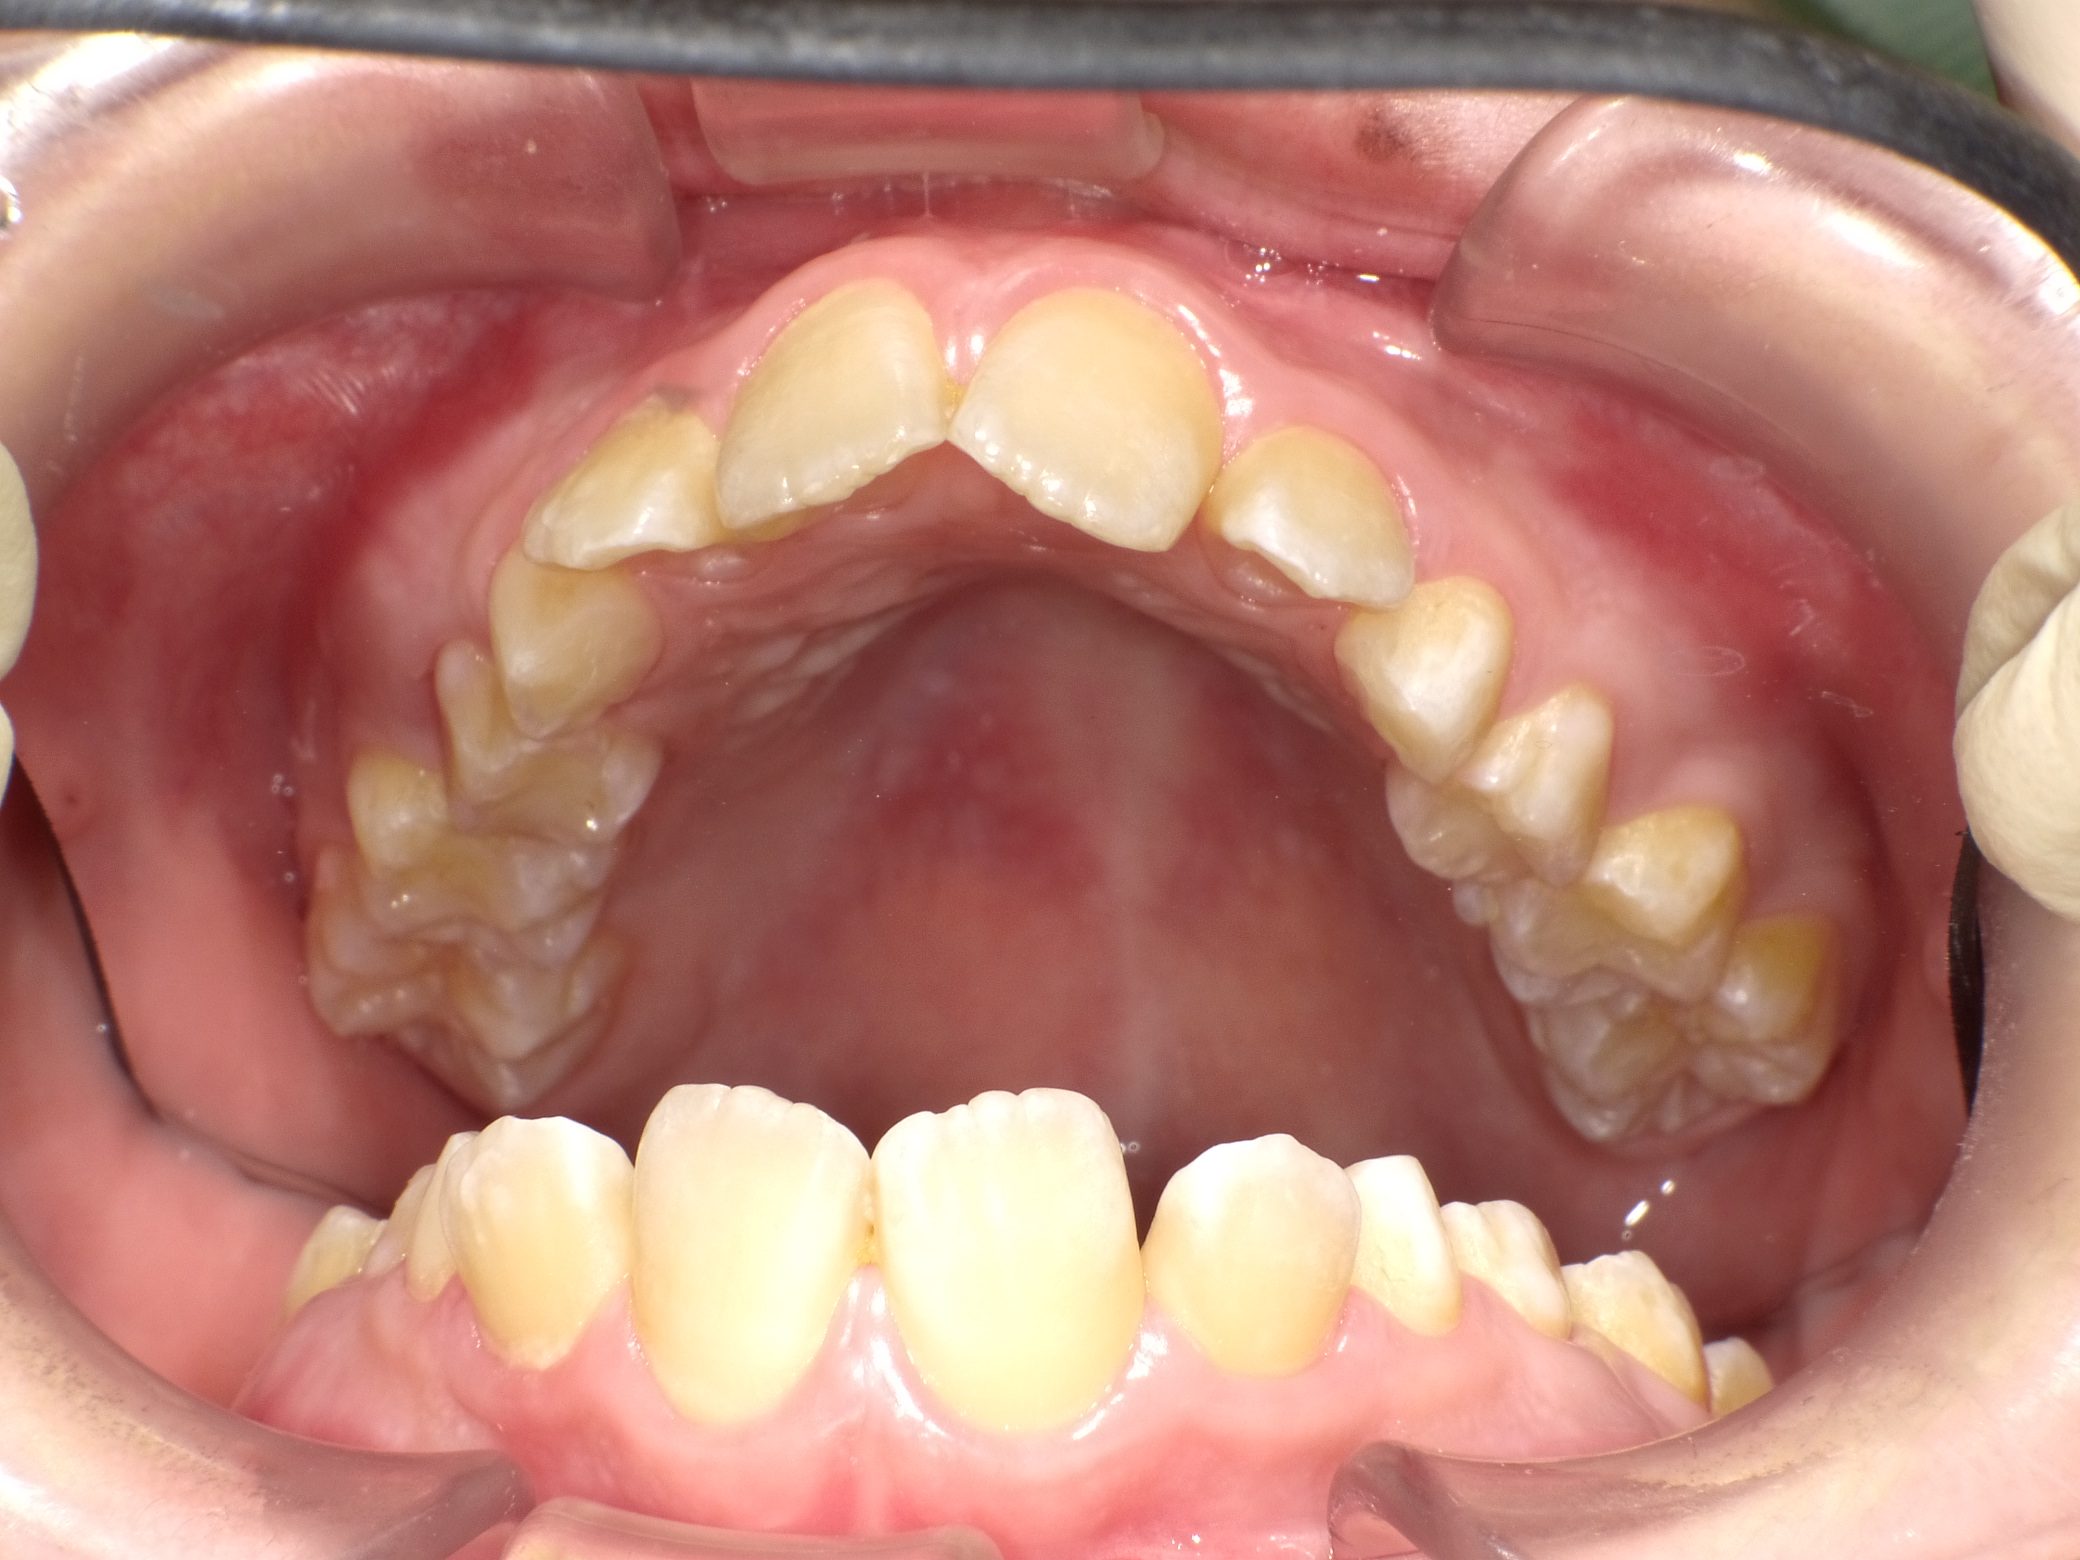

【小学生】 マイオブレース矯正 上顎前突(出っ歯)を改善

小学生で開始

マイオブレース

出っ歯

過蓋咬合

非抜歯

1期治療のみで改善

Before

After

治療期間

2年

治療開始

10歳

種類

マイオブレース矯正

使用装置

コメント

装置の装着と MFT(筋機能療法)をしっかり取り組んでくれました。

舌癖もなおり、後戻りもありません。